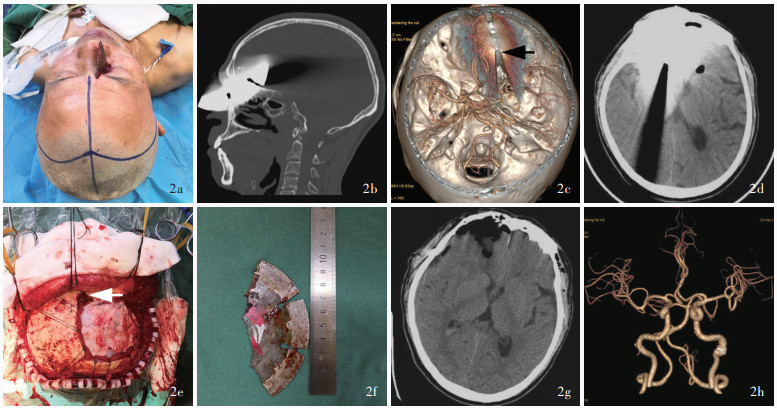

Wu Y , Chen TG , Chen SM , Zhou L , Yuan M , Wang L , Liu ZY , Bi CL , Luo XY , Lan S , Liu JF . Trans-base and trans-vault low-velocity penetrating brain injury: a retrospective comparative study of characteristics, treatment, and outcomes. Chin J Traumatol, 2021, 24: 273- 279.

D'Agostino R , Kursinskis A , Parikh P , Letarte P , Harmon L , Semon G . Management of penetrating traumatic brain injury: operative versus non-operative intervention. J Surg Res, 2021, 257: 101- 106.

Zyck S , Toshkezi G , Krishnamurthy S , Carter DA , Siddiqui A , Hazama A , Jayarao M , Chin L . Treatment of penetrating nonmissile traumatic brain injury: case series and review of the literature. World Neurosurg, 2016, 91: 297- 307.

Huan Y , Hu SJ , Wu S , Wu XQ , He X , Chen YW , Du W , Fei Z , Li B . Investigation of clinical characteristics and death-related factors of non-firarms open head injury. Zhonghua Shen Jing Chuang Shang Wai Ke Dian Zi Za Zhi, 2021, 7: 146- 150.

Xu L , Xu F , Li L , Liu W , Kit Leung GK , Liu B . The surgical strategies and techniques of transorbital nonmissile brain injury. World Neurosurg, 2020, 144: e856- e865.